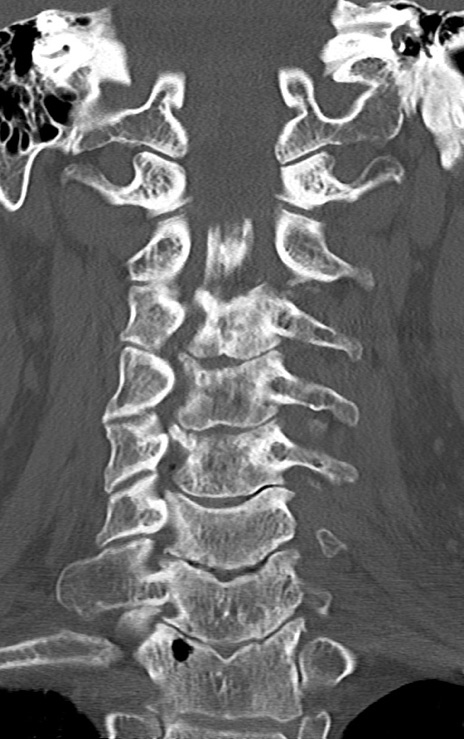

頚椎CT

矢状断像